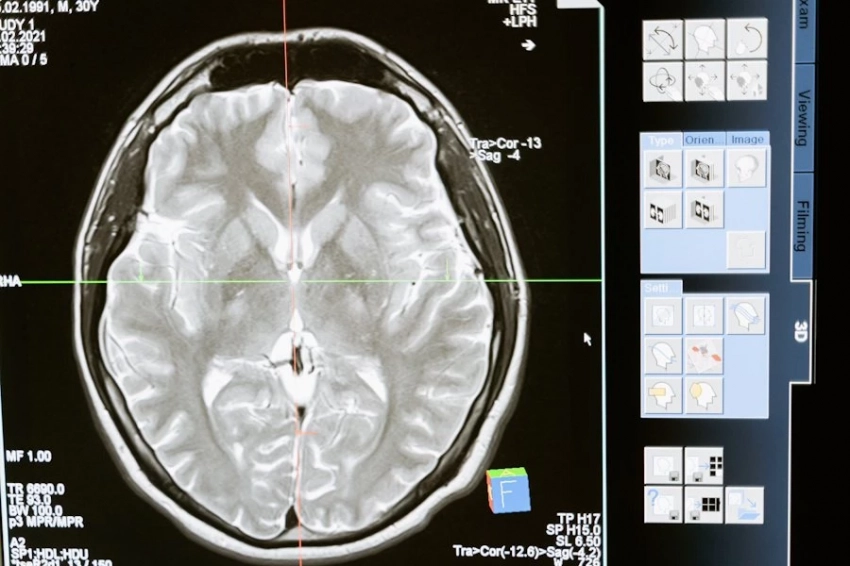

Новое исследование в Lund University (Швеция) показало, что привычка к чтению может значительно влиять на структуру мозга, особенно в областях, связанных с обработкой языка. У людей с навыками чтения обнаружены уникальные изменения в левом полушарии. Это, в частности, передняя височная доля, которая помогает связывать значения слов, и извилина Гешля, играющая ключевую роль в восприятии звуков языка.

Согласно изданию Neuroscience News, ученые отмечают, что чтение развивает толщину коры мозга в этих областях, что напрямую связано с лучшими навыками интерпретации и анализа информации. Интересно, что даже такие, на первый взгляд, «слуховые» зоны, как извилина Гешля, связаны с чтением, так как этот процесс требует фонологической обработки — способности сопоставлять буквы и звуки.

Исследование подчеркивает пластичность мозга: регулярное чтение со временем изменяет его структуру, помогая эффективнее справляться с когнитивными задачами. Однако есть и тревожные данные — всё меньше людей читают ради удовольствия. Согласно опросам, половина взрослых в Великобритании не читают книги регулярно, а среди молодежи этот показатель ещё ниже.